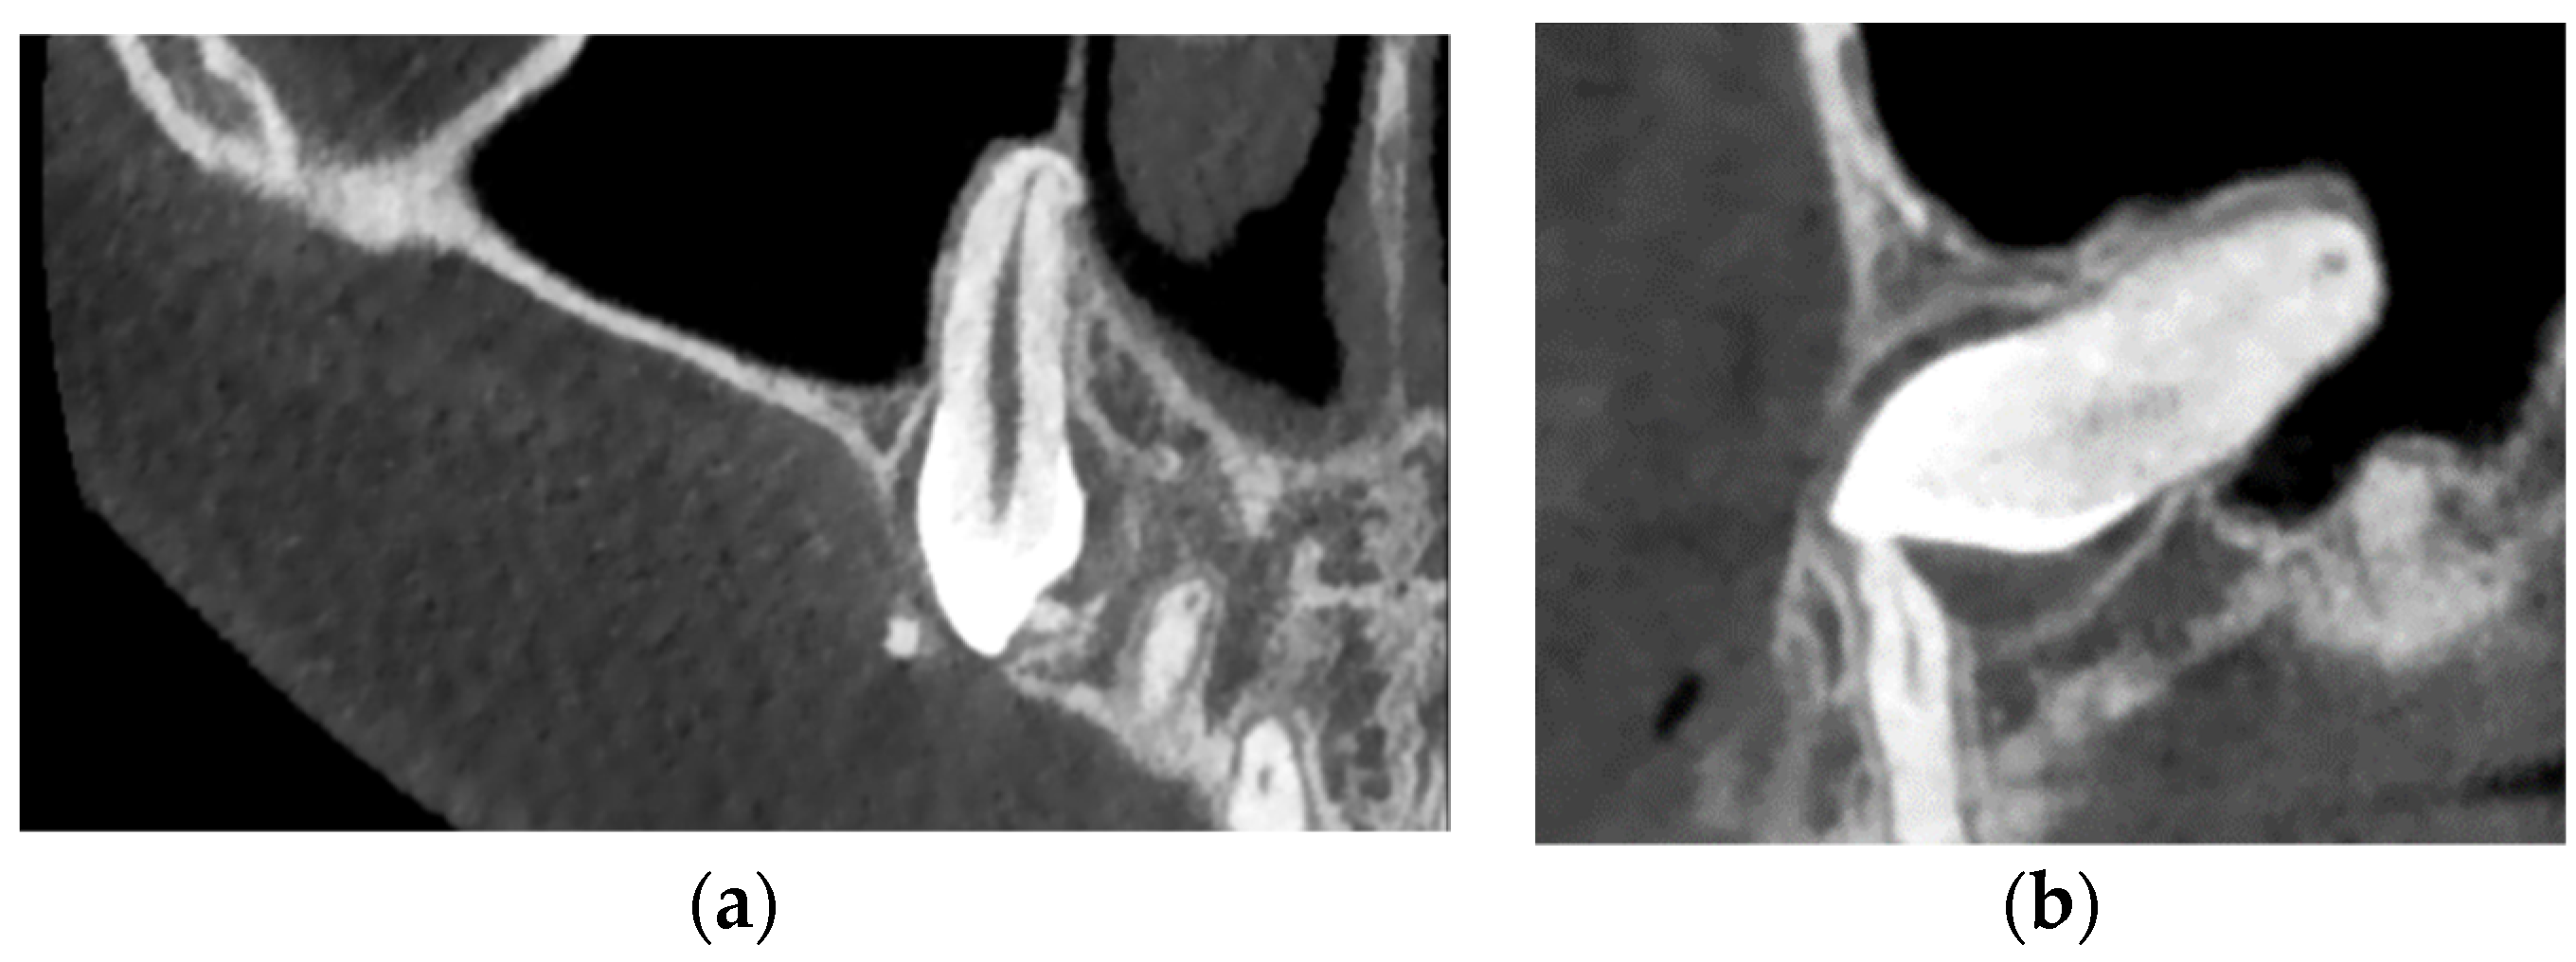

| Case Number | Summary of X-ray Findings |

| Case 1 |

|